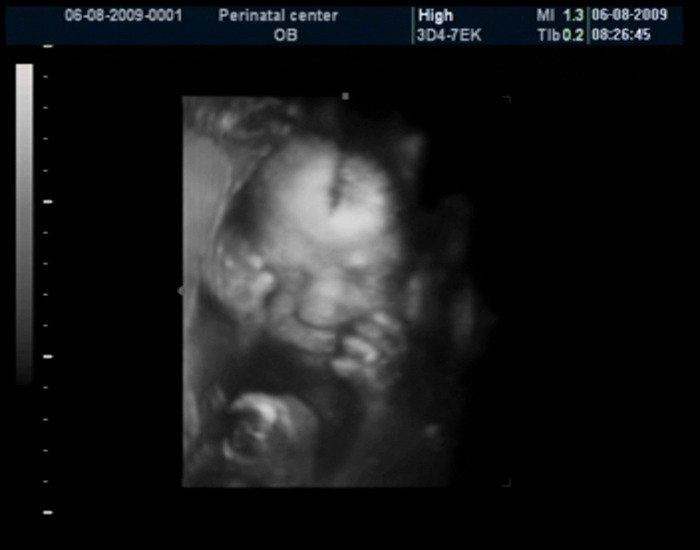

27-hafta

Tug‘ilishga 13 hafta bor